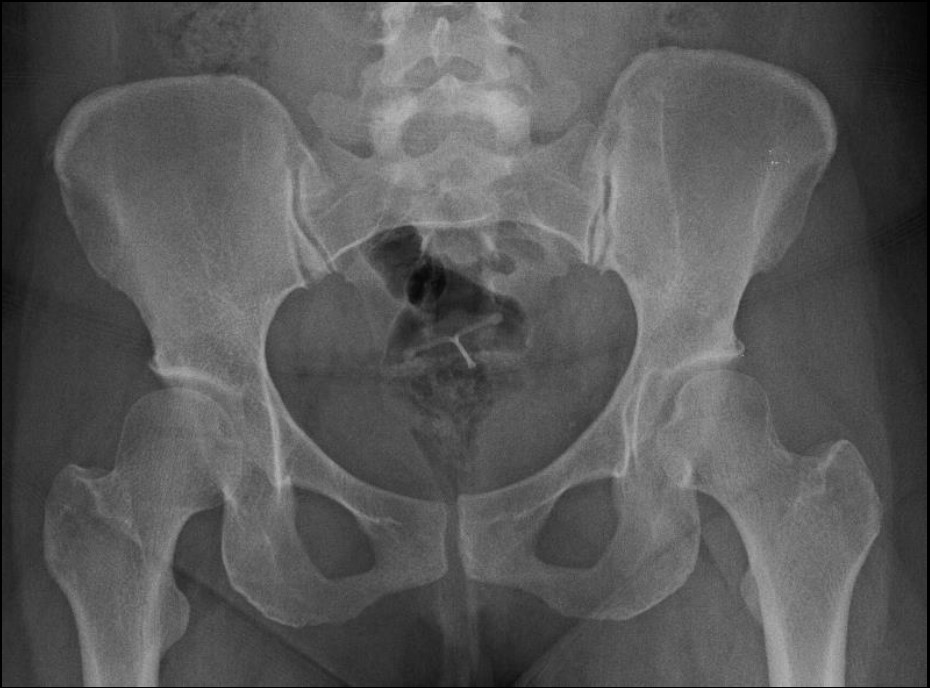

Imagerie de la hanche :  variantes et anomalies fréquemment asymptomatiques